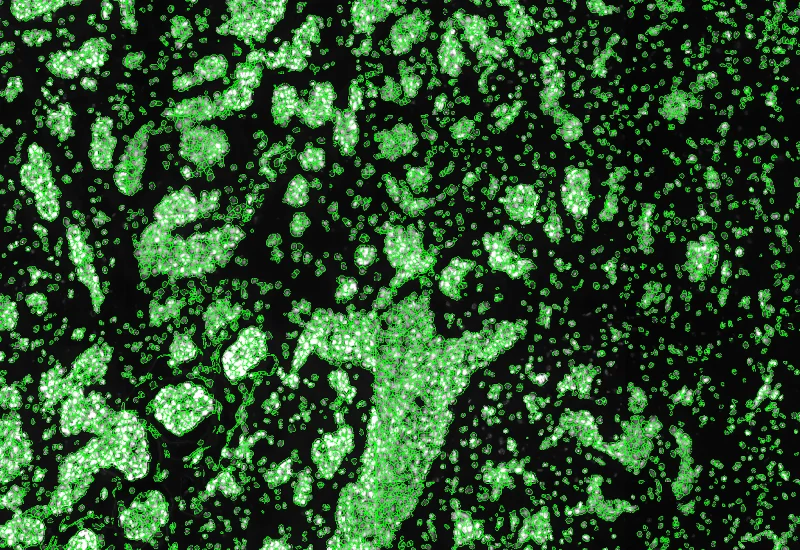

Original Image

Nuclei detection

Tumor foci detection

The IF Tumor Foci Angio App is able to identify single cells as well as to segment tissues into tumor foci and blood vessels based on appropriate markers. It applies proximity maps to identify nuclei close to blood vessels. It measures the number of nuclei that are at a certain distance relative to blood vessels, the number of nuclei in the different morphological entities and the area of the morphological entities.

Detect single nuclei and segment tissue into tumor foci and blood vessels, apply proximity mapping to quantify nuclei distances to vessels, and measure compartment areas and nuclei distribution.